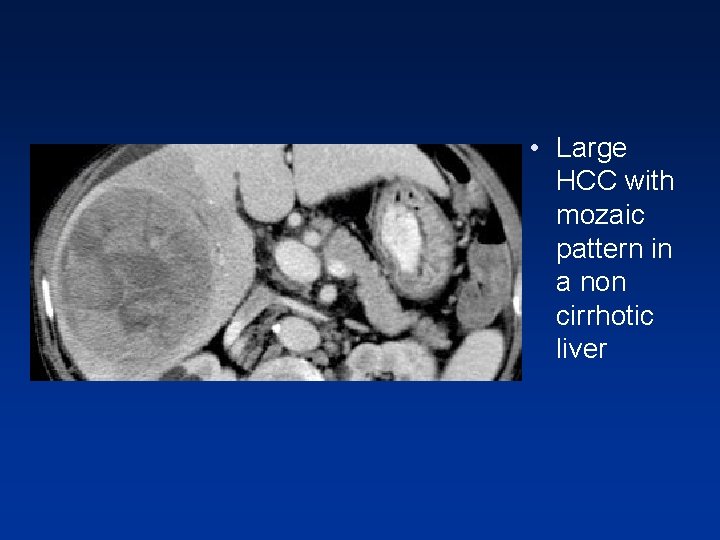

• Any hypervascular lesion in a cirrhotic liver is hepatocellular carcinoma untill proven otherwise. • HCC may be solitary, multifocal or diffusely infiltrating. • Large HCC typically have a mosaic appearance due to hemorrhage & fibrosis.

• HCC is a silent tumor, so if patients don’t have cirrhosis or hepatitis C , you will discover them in a late stage. • They tend to be large with mozaic pattern , a capsule , hemorrhage and necrosis. • HCC become isodense or hypodense to liver in the portal venous phase due to fast wash-out • On delayed images, the capsule and sometimes septa demonstrate prolonged enhancement.

• Large HCC with mozaic pattern in a non cirrhotic liver